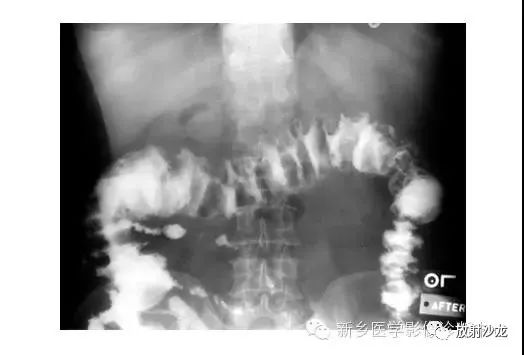

上张X线片在小肠靠近横结肠处出现几圈膨大后合并狭窄。术中发现该患者由于肠系膜动脉栓塞致小肠肠襻坏疽。